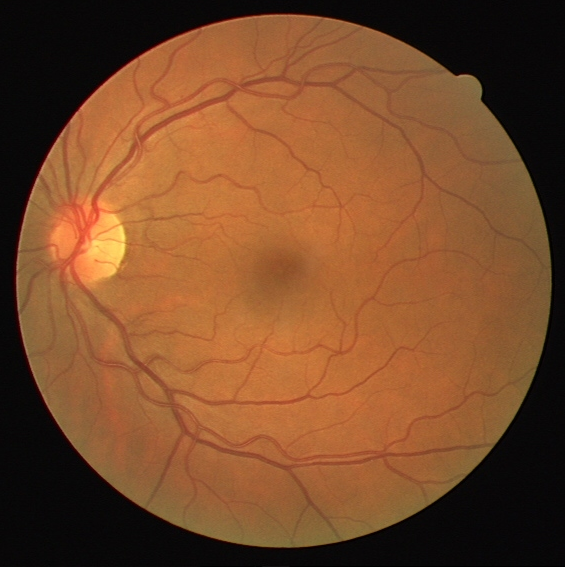

Vessel segmentation in fundus is a key diagnostic capability in ophthalmology, and there are various challenges remained in this essential task. Early approaches indicate that it is often difficult to obtain desirable segmentation performance on thin vessels and boundary areas due to the imbalance of vessel pixels with different thickness levels. In this paper, we propose a novel two-stream Meticulous-Processing Network (MP-Net) for tackling this problem. To pay more attention to the thin vessels and boundary areas, we firstly propose an efficient hierarchical model automatically stratifies the ground-truth masks into different thickness levels. Then a novel two-stream adversarial network is introduced to use the stratification results with a balanced loss function and an integration operation to achieve a better performance, especially in thin vessels and boundary areas detecting. Our model is proved to outperform state-of-the-art methods on DRIVE, STARE, and CHASE_DB1 datasets.

Fundus image analysis serves as a key and non-invasive tool in the diagnosis and treatment of many ophthalmological and cardiovascular diseases. Additionally, with the developing of deep learning methods, many network architectures based on U-Net or adversarial procedures have been proposed to learn the end-to-end relations between an original image and a ground-truth binary mask manually labeled by experts. Maninis [1] proposed Deep Retinal Image Understanding (DRIU) which fine-tuned VGGNet. During the progress of deep learning approaches, segmentation performance on thin vessels has become a great challenge and focus. Zhang et al. [2] propose a U-Net architecture (ML-UNet) [3] for multi-label segmentation of thin and stem (thick) vessels. Yan et al. [4] propose a novel segment-level loss in addition to the pixel-level loss to train a U-Net architecture (JL-UNet), and report increased segmentation accuracy for thin vessels. Yet, the work of Zhang et al. [2] and Yan et al. [4] which propose an essentially multi-label miscellaneous network, do not have an end-to-end network which dedicated for specific binary classification tasks focusing different types of features. Additionally, Gu et. al [5] propose a context encoder network (CE-Net) to better extract the high-level information of the image, while the CE-Net loses to focus on thin and boundary areas.

In this paper, we inspect the rationale behind this problem from a perspective of data balancing. The reason that ordinary neural networks did not obtain desirable segmentation performance on thin vessels and boundary areas is that vessel data are suffered from imbalance internal to an assumed identical class (vascular or non-vascular). Vessels with different thickness levels may have different features for identification and localization, making them essentially different classes in a segmentation task. Therefore, balancing across these classes becomes an important work to avoid bias in learning. However, such balancing remains challenging as in most available segmentation datasets, the ground-truth mask is binary, providing no immediate information regarding thickness levels. In view of this challenge, we propose a novel morphological model that automatically segments and classifies (stratifies) ground-truth masks into strata regarding vessel thickness levels using hierarchical opening operations. In order to further increase the segmentation performance, we also propose a two-stream model that learns both general retinal vascular features and those specific to thin vessels and boundary areas by processing both all strata and only the thin vessels (the following ”thin vessels” refer to both thin vessels and boundary areas) stratum. The results from the two streams are united (pixel-wise ORed) to output the final result.

We evaluate our model on three standard datasets widely used for the retinal vessels segmentation task. All of these three datasets contain no annotations of vessels thickness levels and are therefore appropriate for our stratification model to process. DRIVE [10] 111https://www.isi.uu.nl/Research/Databases/DRIVE/ contains 40 color fundus (CF) images with manually labeled ground-truth masks, where 20 images for training and use the remaining 20 images for testing. To reduce selection bias, we repeat the experiment 5 times and report the averaged result. STARE [11] 222http://cecas.clemson.edu/~ahoover/stare/ contains 20 manually labeled CF images. We report average results on 4-fold cross-validation with 15 training samples and 5 testing samples. CHASE_DB1 [12] 333https://blogs.kingston.ac.uk/retinal/chasedb1/ contains 28 labeled samples, where we report average performances on 4-fold cross-validation.

To justify the performance of our model, we compare the 4 metrics with 8 representative previous works from all 3 open-access datasets. The comparison results presented in Table 1 show that our MP-Net model outperforms the state-of-the-art methods regarding accuracy and in all three datasets, which meter the practical prediction quality and the overall prediction quality independent on thresholding specifications. The advancement is greater in the DRIVE dataset. It’s related to the fact that the DRIVE dataset contains more thin vessels, which is the main target of our model. Specificity is also the highest in DRIVE and CHASE_DB1 while sensitivity is highest in STARE. Particularly, our method outperforms ML-UNet [2] and JL-UNet [4] which adopt a different multi-class approach to also especially tackle the thin-vessels challenge. Figure 2 shows an example of our segmentation maps on DRIVE. As can be seen, most thin vessels and boundary areas have been meticulously picked up.